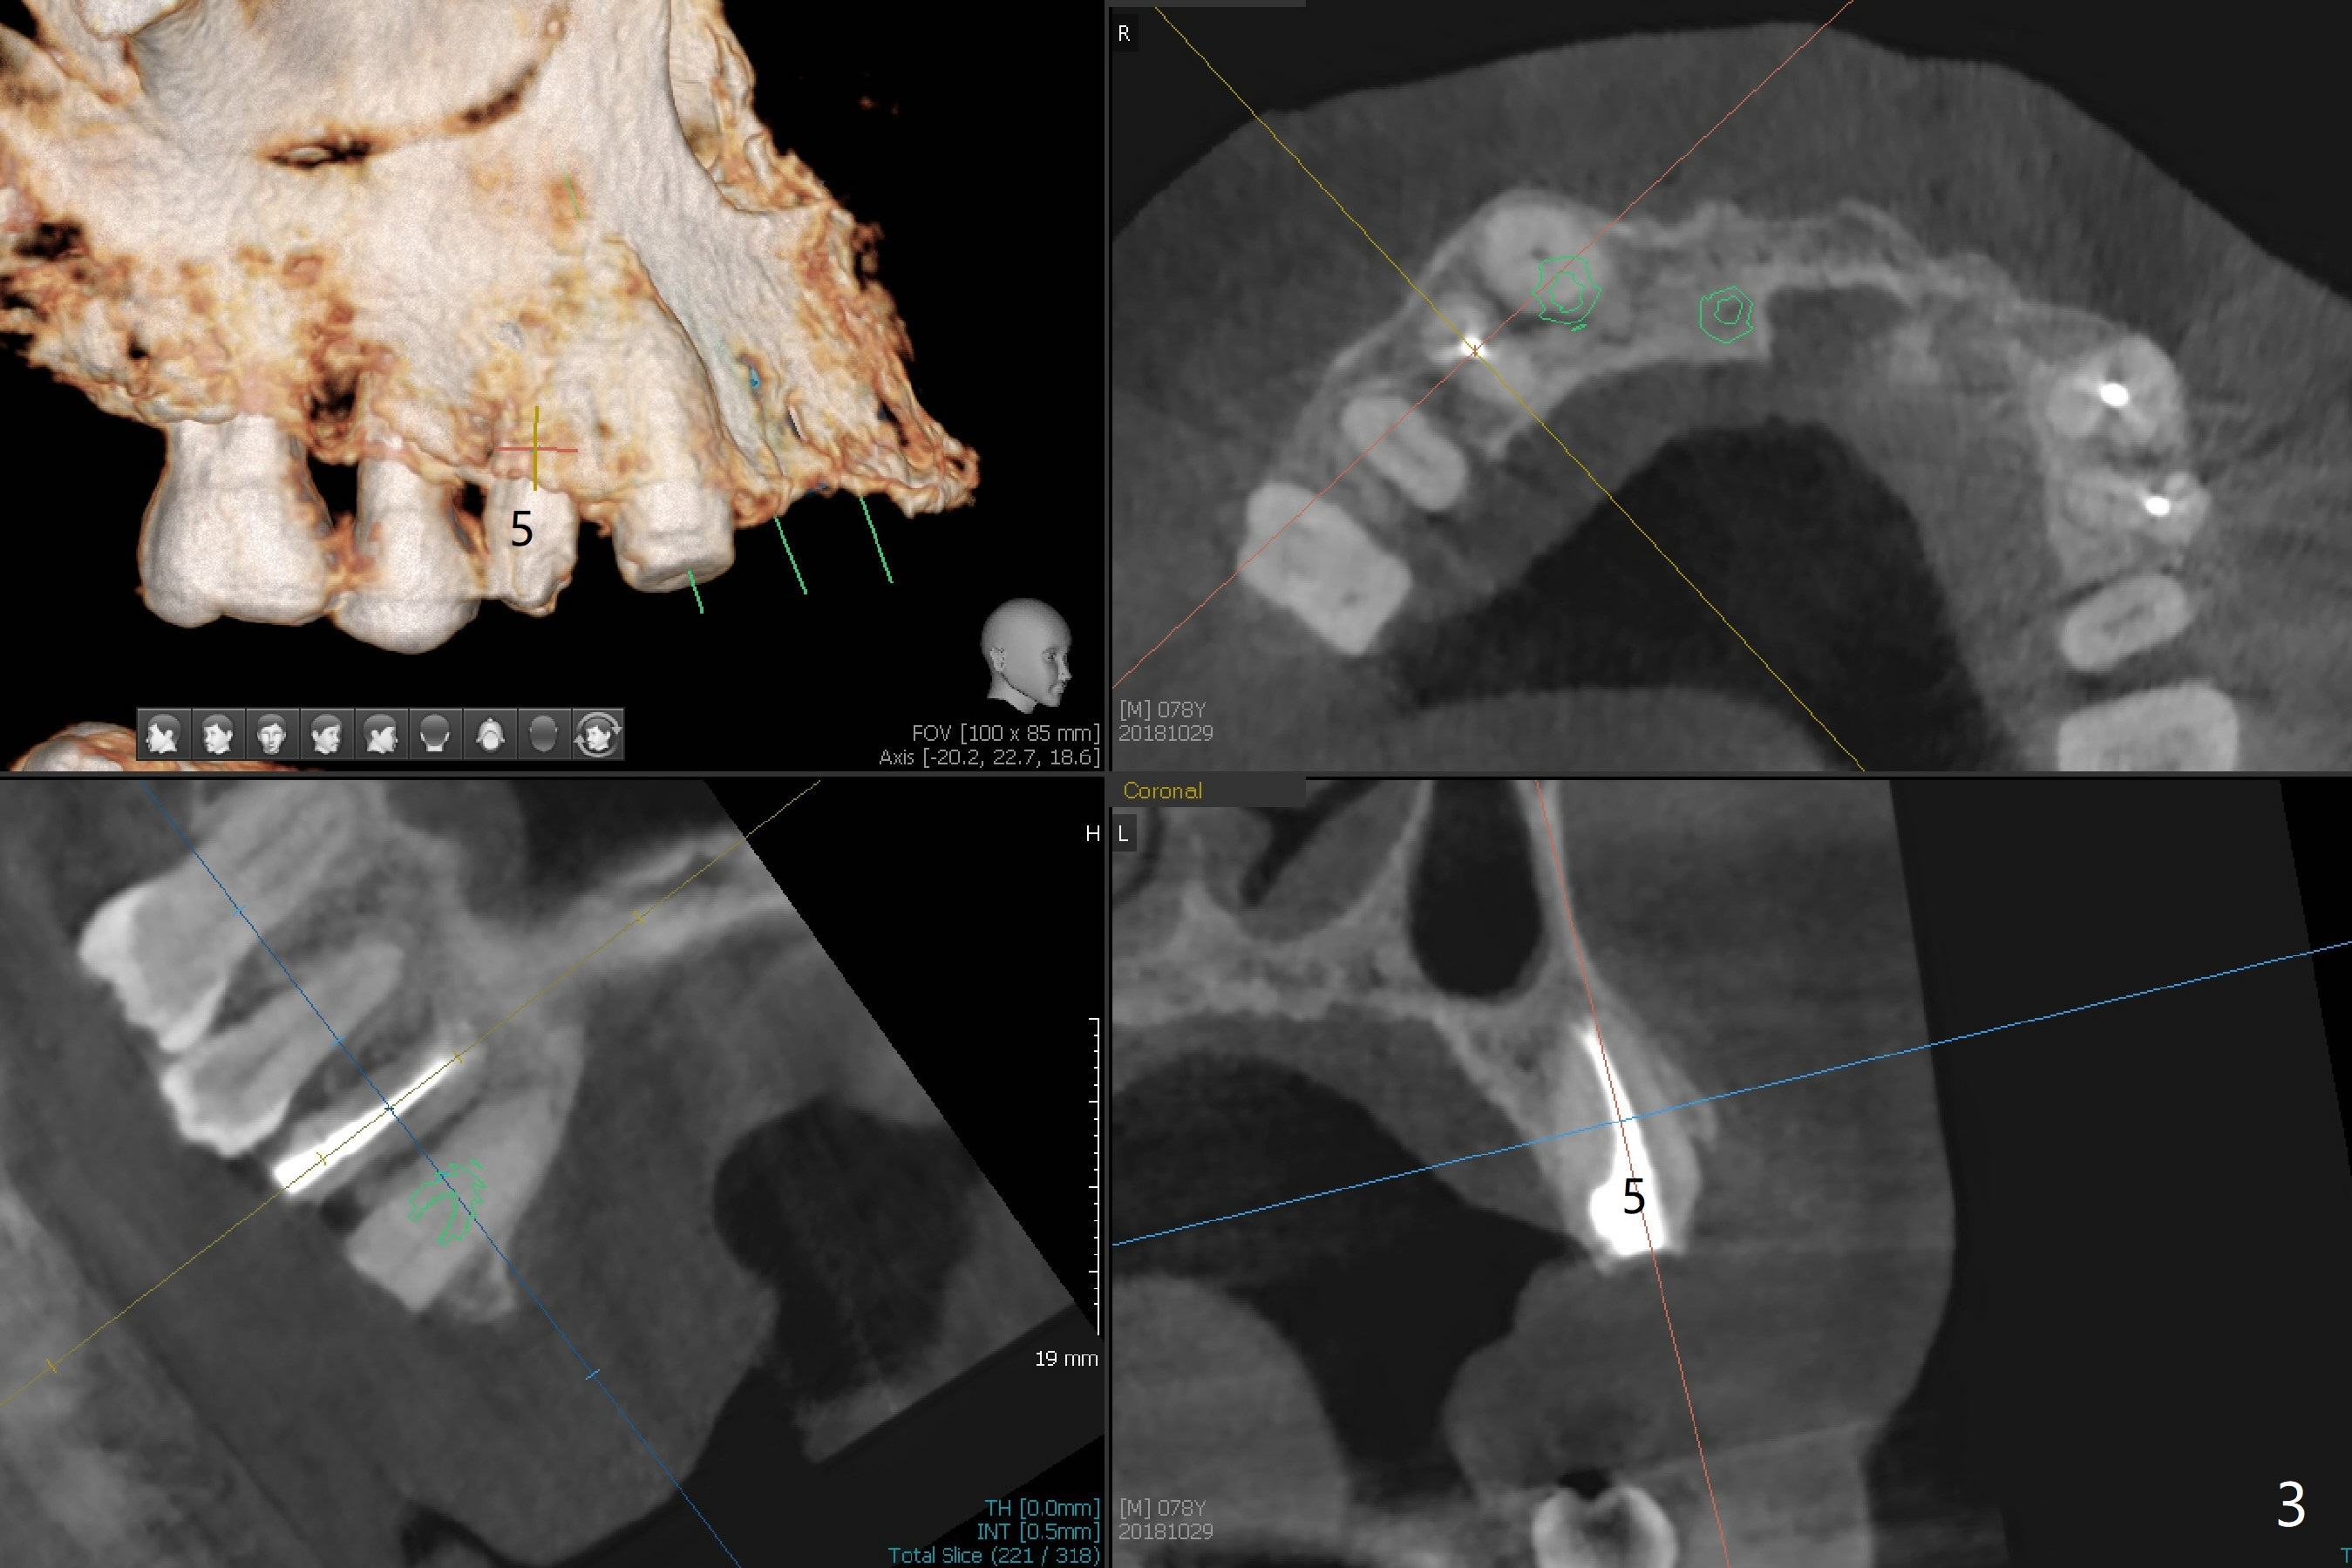

A 78-year-old man's 8 unit FPD dislodges (#5-12, Fig.1). Three of 4 abutments seem to be non-salvageable (#6,11,12 fractured equigingival, extraction, immediate implants). For restoration, implant will be placed at #8 and 9 as well. Implant FPDs will be fabricated at #6-8 and 9-11 (Fig.2) with #5 (with build up or prefabricated post) and 12 single unit crowns to better withstand deep overbite and overjet. After discussion with lab, a major change will be implants to be placed at #7 and 10 instead of #8 and 9 (narrow ridge). The implant at #7 will be a 1-piece (3 mm in diameter), whereas the rest 2-piece (3.5 mm). The abutment of IS 1-piece implant is 10 mm in length, while that of DIO's 5 mm. The former will be used if the vertical space is sufficient.